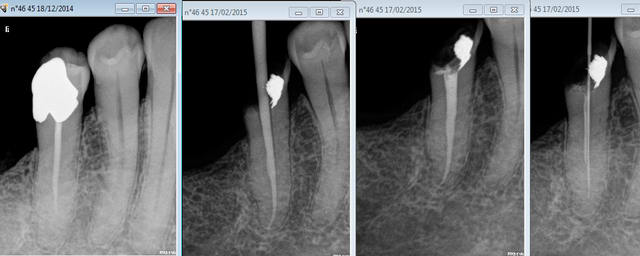

Une petite dernière pour la route de remise en question. -)))

Je m'excuse pour la non pose de digue, le patient ayant refusé les devis de désobturation endodontique (pas réussi à mettre de crampon sans) ainsi que la reconstitution pré-endo, c'était pas remboursé ! -))))

Attention au S1, il faut vérifier qu'il ne se dé-vrille pas au bout, j'en ait balancé 2 dans le cas ci dessus. pas hésiter à passer une lime 10 manuelle si ca force ( pas besoin de mesurer la LT avec elle ne risque pas de défoncer l'apex).